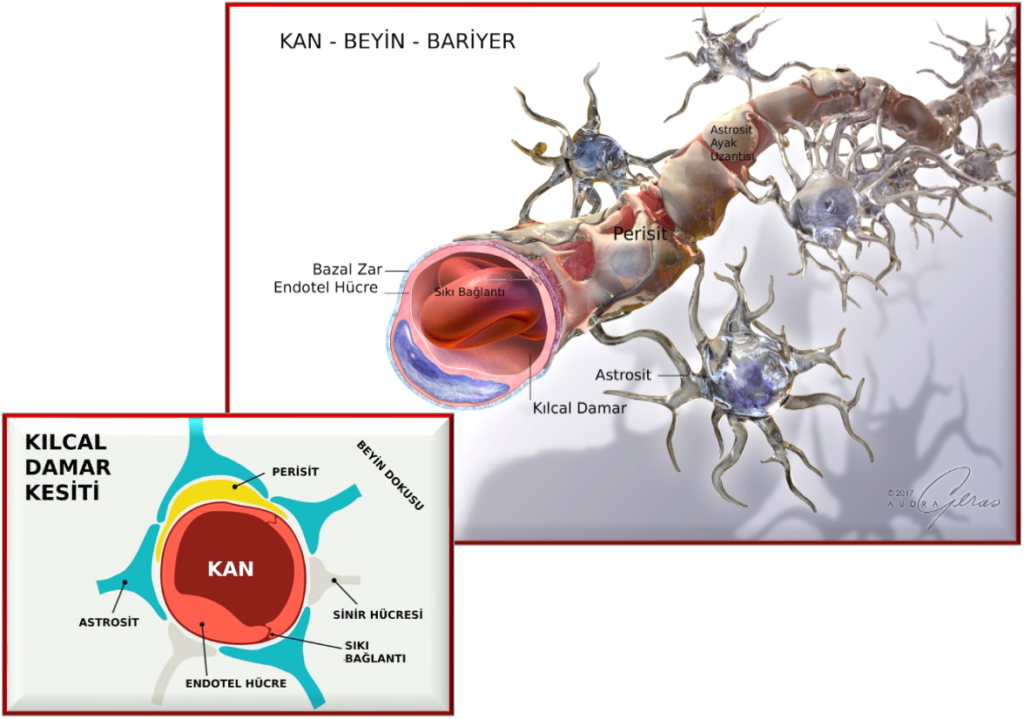

Bu mucize sistem resimde görüldüğü üzere şu yapılardan oluşur: [1]

- Kılcal damarların iç yüzeyini kaplayan endotel hücreleri

- Damar duvarının dış tabakasındaki perisit hücreleri,

- Beynin gri maddesinde bulunan yıldız şeklindeki astrositik hücreler,

- Beynin kan damarlarının iç yüzeyindeki epitel hücrelerinin tabanını kaplayan, onları alttaki bağ dokusundan ayıran ve ayrıca sinir hücrelerini örten bazal membran,

- Koroid pleksus: Beyni ve omuriliği çevreleyen beyin omurilik sıvısını üretir,

- Pisiform ve araknoid zarlar: beyni çevreleyen üç katmanlı zarın iç iki katmanını oluşturur.

KAN-BEYİN BARİYERİNİN YAPISI

Kan-beyin bariyeri, vücuttaki işlevine uygun olarak yaratılmış karmaşık hücresel yapılardan oluşur. Bariyer sayesinde maddelerin beyin hücrelerine geçişi fiziksel olarak güçlü bağlarla, metabolik olarak da enzimlerle kontrol edilir. Merkezi sinir sisteminin kılcal damarları, onları vücuttaki kılcal damarlardan ayıran birkaç özelliğe sahiptir. Bunlardan biri, beyin kılcal damarlarını kaplayan hücreler (endotel) arasındaki sıkı bağlantılar ve bu kılcal damarların üzerinde sürekli bir zarın (bazal membran) bulunmasıdır. Ancak ilginç bir şekilde, kan-beyin bariyerinin endotel hücreleri arasında yüksek elektrik direnci vardır. Diğer dokularda 3-33 W/cm2 olan direnç, kan-beyin bariyerinde 1500-2000 W/cm2’ye kadar yükselir. Bu elektrik alanı, sıvıların ve iyonların hücre içine ve dışına taşınmasına bir engel oluşturarak geçirgenliği azaltır. Ayrıca kan-beyin bariyerinde, vücuttaki diğer kılcal damarlarda olduğu gibi molekül ağırlığı 10.000’den (g/mol) az olan maddelerin geçebileceği delikler veya yarıklar bulunmaz. [3]